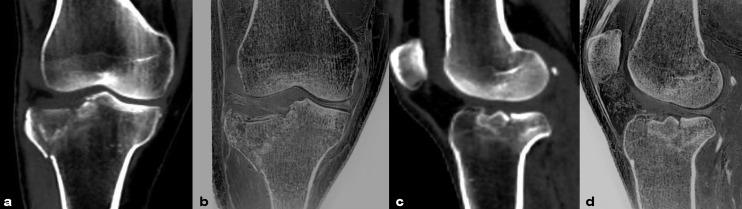

To explore the consistency of FRACTURE (Fast-field-echo Resembling A CT Using Restricted Echo-spacing) MRI and X-Ray/computerized tomography (CT) in the evaluation of bone injuries in knee and ankle joints.

From Nov. 2020 to Jul. 2023, 42 patients with knee joint or ankle joint injuries who underwent FRACTURE MRI examinations were retrospectively collected. 11 patients were examined by both X-Ray and FRACTURE examinations. 31 patients were examined by both CT and FRACTURE examinations. The fracture, osteophyte, and bone destruction of the joints were evaluated by two radiologists using X-Ray/CT and FRACTURE images, respectively. Kappa test was used for consistency analysis.

The evaluation consistency of fracture, osteophyte and bone destruction via X-Ray and FRACTURE images by radiologist 1 were 0.879, 0.867 and 0.847 respectively, and for radiologist 2 were 0.899, 0.930, and 0.879, respectively. The evaluation consistency of fracture, osteophyte and bone destruction via CT and FRACTURE images by radiologist 1 were 0.938, 0.937 and 0.868 respectively, and for radiologist 2 were 0.961, 0.930, and 0.818, respectively.

For fracture, osteophyte, and bone destruction of knee and ankle joints. FRACTURE MRI showed a high consistency with X-Ray/CT examinations.